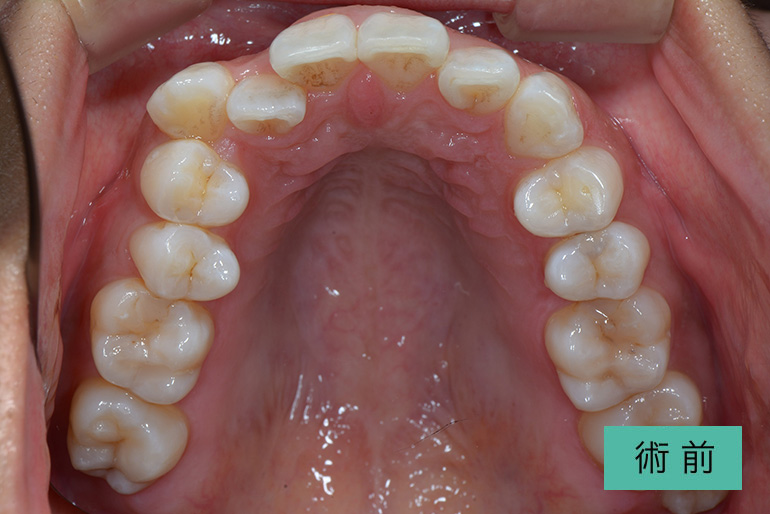

オールセラミック①

| 治療内容 | 上顎インビザライン矯正 右上1番から左上の2番のセラミック冠 上顎前歯の叢生、右上犬歯の捻転の改善のため、上顎のみインビザライン矯正を行なった また、根尖病巣があった為補綴を除去、顕微鏡根管治療を行い、セラミック冠を装着した |

| 治療期間・回数 | 約8ヶ月、15回(インビザライン矯正) 約4ヶ月、6回(補綴治療) |

| 費用(税込) | ¥275,000 (上顎インビザライン矯正) ¥495,000(165,000/1本)(補綴費用) ※自由診療 |

| リスク・副作用 | 疼痛、補綴物の脱落、咬合違和感、破折 |